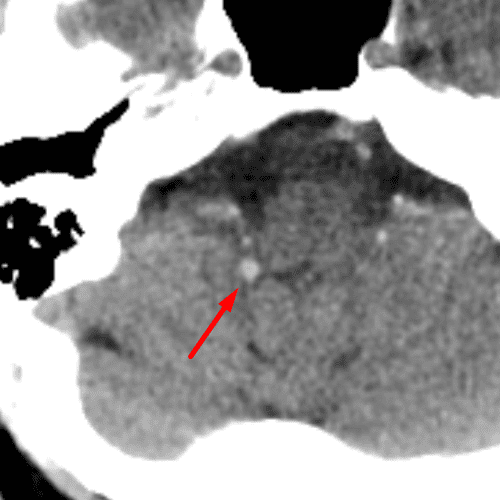

Ecchordosis Physaliphora

Case 16